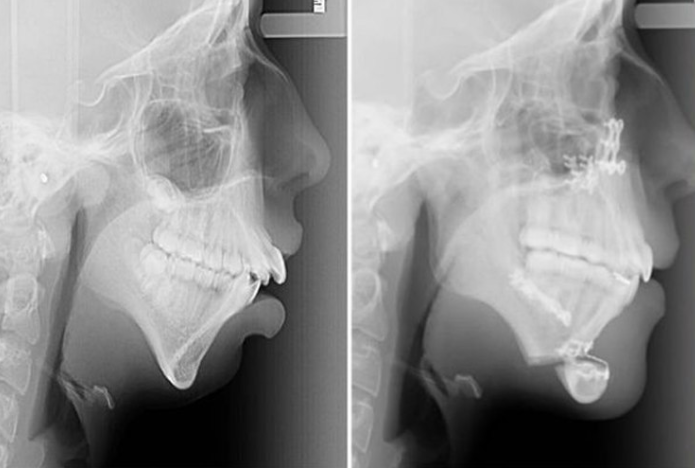

▼正颌手术X光照片及效果